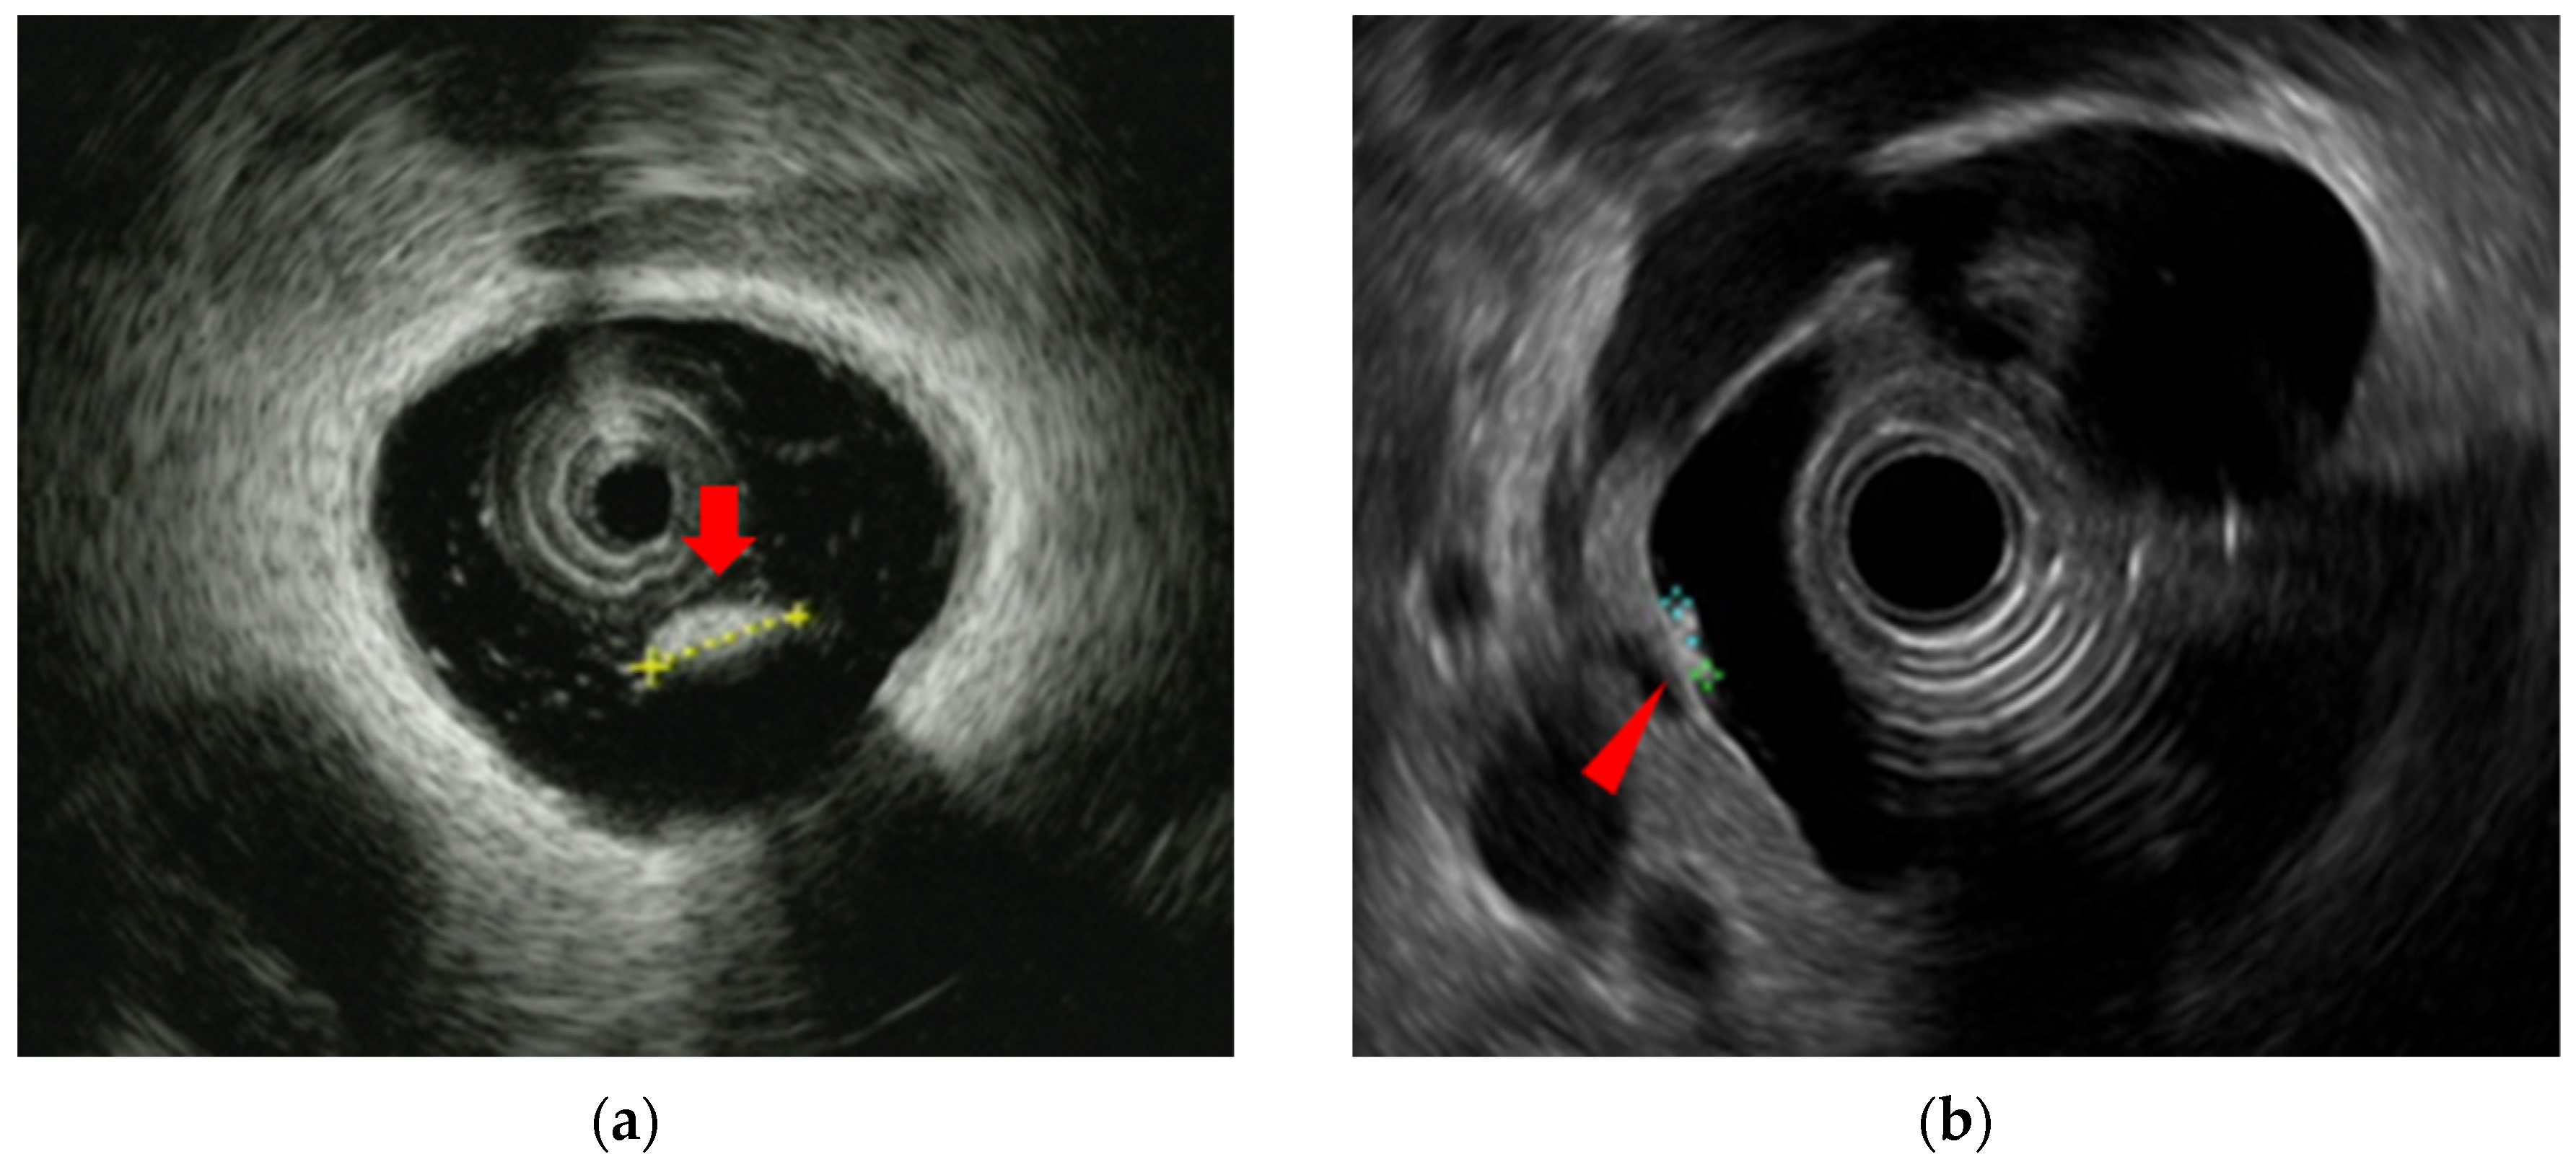

EUS and IDUS can clearly delineate the structure of the bile duct wall. The normal bile duct wall structure consists of two to three layers, with the inner layer being hypoechoic and the outer layer being hyperechoic [Figure 4]. The inner hypoechoic layer reflects the mucosal layer, fibromuscular layer, and part of the subserosal layer. The outer hyperechoic layer corresponds to the subserosa and serosa. If this lateral hyperechoic layer is irregular or interrupted, it should be considered suspicious for invasion.

The gallbladder wall consists of two layers: the inner layer includes the mucosa, the muscularis propria and a part of the subserosa, which appear hypoechoic; and the outer layer consists of a part of the subserosa and the serosa, which appear hyperechoic. EUS can usually depict these two layers [47] [Figure 4].

Figure 4. Image of the normal structure of the biliary duct wall and gallbladder wall: (a) (b) Image of the biliary duct wall on intraductal ultrasound and the gallbaldder wall on endoscopic ultrasound; (c) (d) Red arrows show inner hypoechoic layer corresponding to mucosa, muscularis propria, and a part of the subserosa. Yellow arrows show outer hyperechoic layer corresponding to a part of the subserosa and the serosa.